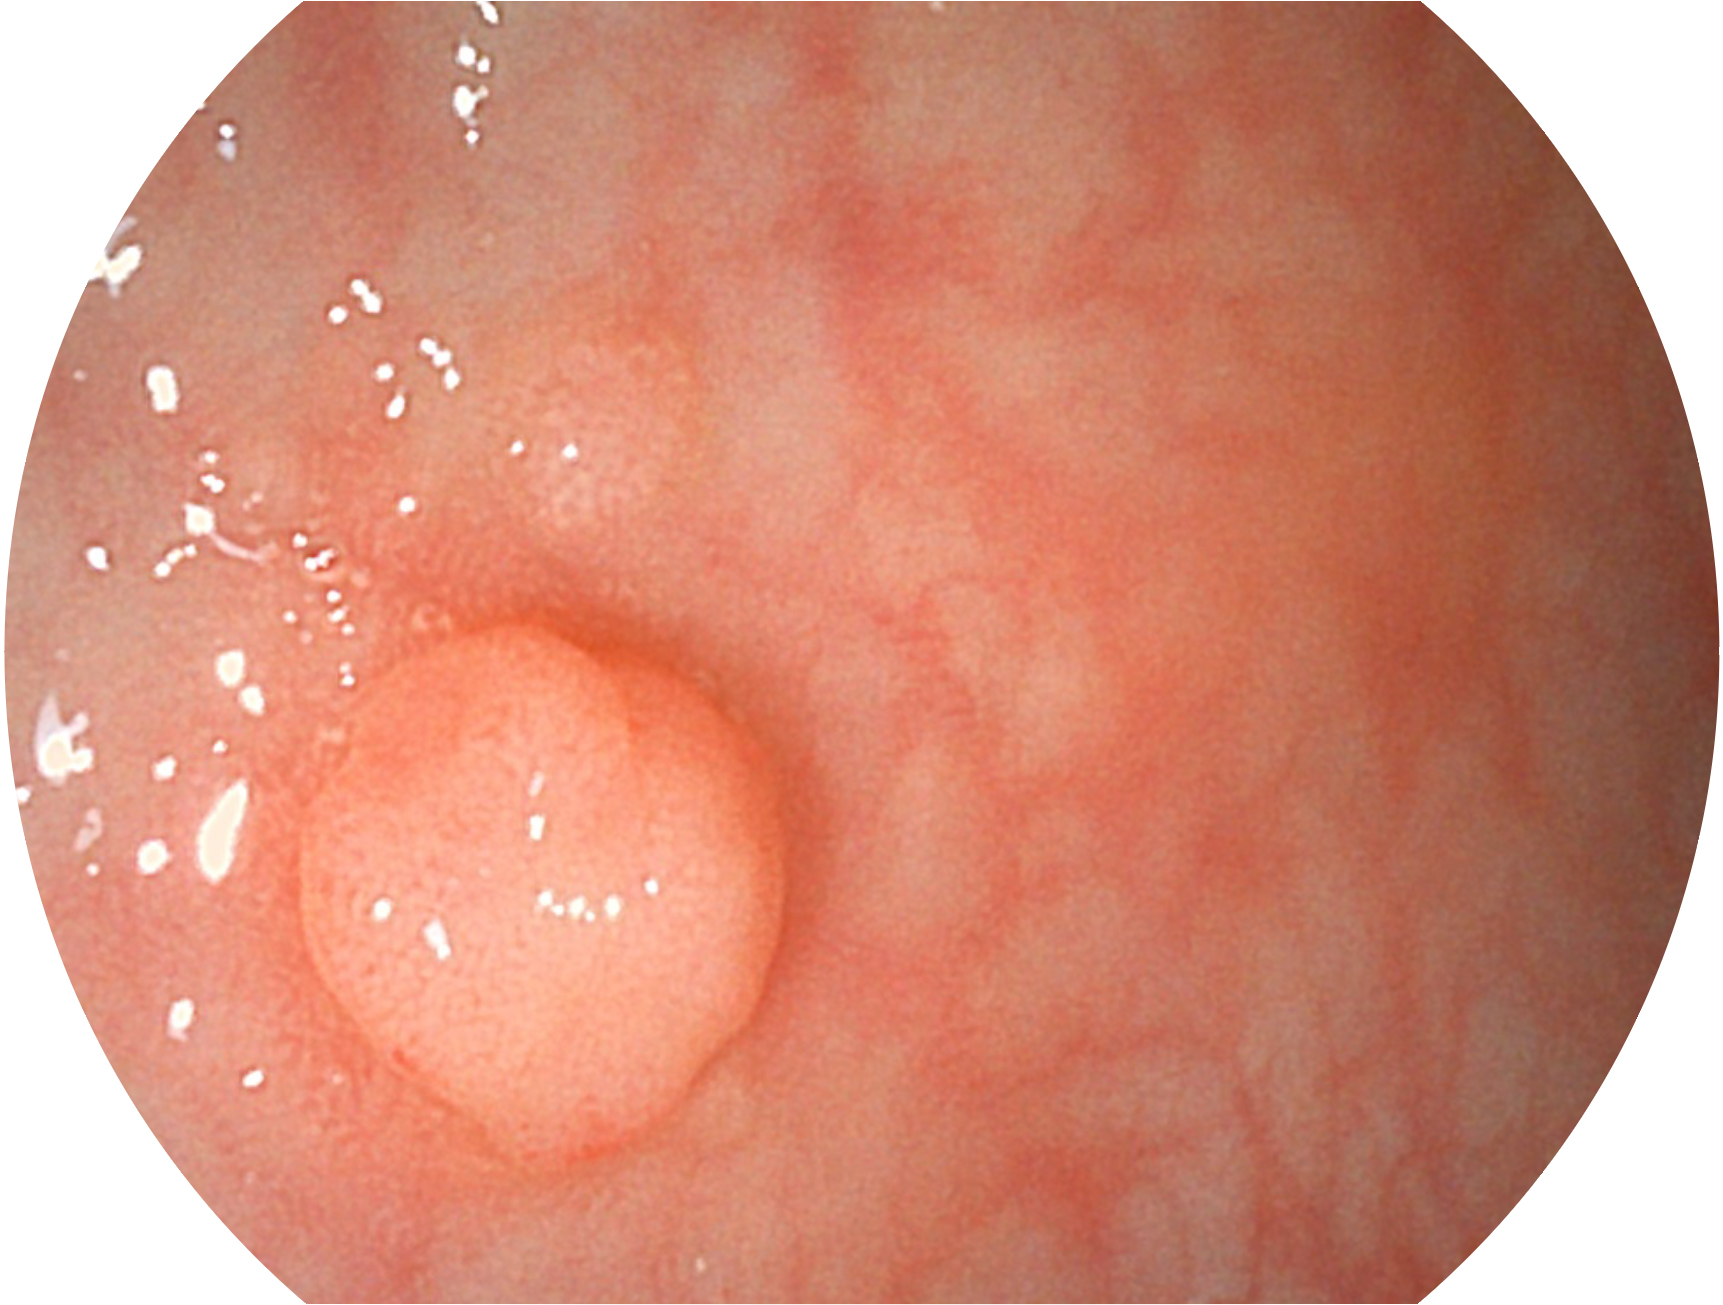

DB中国旗舰官方网站新开发的内镜染色技术,主要是基于多波长LED 光源的开发,VLS-55Q 四波长LED 光源是由四个不同颜色的LED光按照相应照明模式所规定的特定发光比例进行合束后形成,合束后形成的照明光的光谱由红光、绿光、蓝光及蓝紫光这四个不同的波段范围构成。具有更高光谱自由度,通过光谱比例的控制,实现了聚谱成像技术,英文全称为“Spectral Focused Imaging, SFI”,缩写为“SFI”和光电复合染色成像技术,英文全称为“Versatile Intelligent Staining Technology, VIST”,缩写为“VIST”。